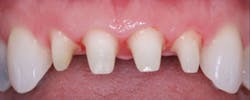

Figure 4: Patient with splinted anterior crowns and large carious lesion on lateral incisor had moderate constant pain

Figure 5: Patient had moderate postoperative pain after tooth preparation appointment.

Figure 6: Patient had almost no postoperative pain after tooth preparation appointment. Both patients in Figures 5 and 6 had same apparent trauma during tooth preparation, but they reported very dissimilar postoperative pain.